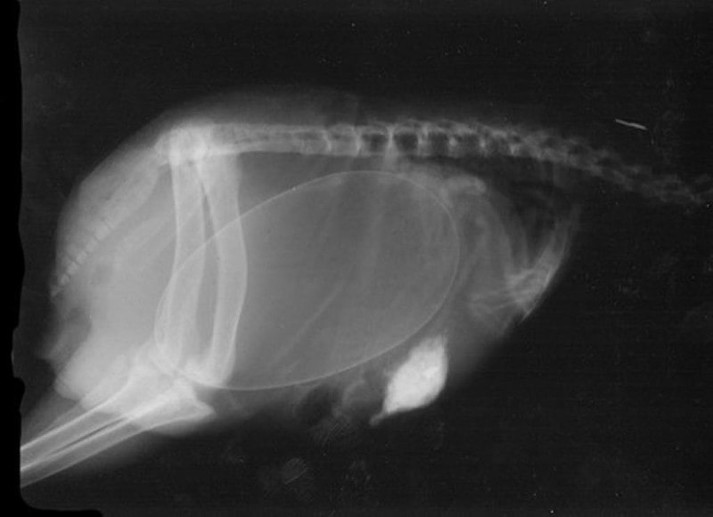

15 удивительных рентгеновских снимков беременных животных

Специалисты, которые по долгу своей работы наблюдают животных, готовых принести потомство, поделились этими удивительными рентгеновскими и ультразвуковыми снимками.